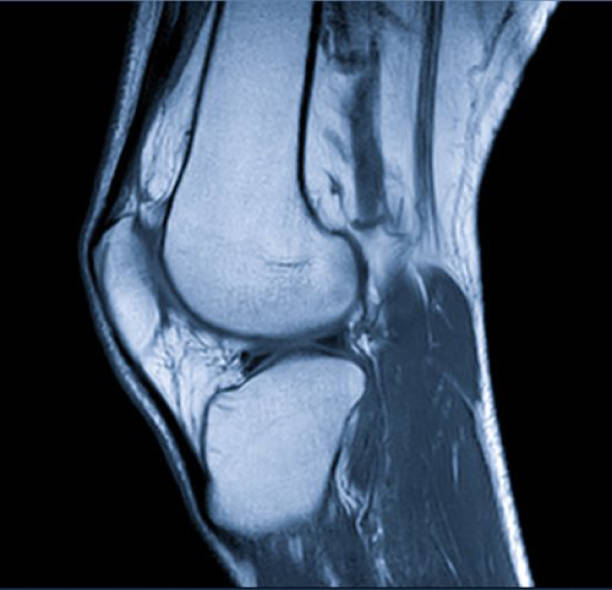

Knees bear the brunt of our movement, supporting our weight and providing the mobility needed for walking, running, climbing stairs, and more. However, this critical joint is highly susceptible to pain and injury due to its constant use and exposure to stress. Conditions like arthritis (osteoarthritis or rheumatoid arthritis), ligament injuries (ACL or MCL tears), meniscus tears, or overuse injuries can lead to significant discomfort. Pain in the knee often starts as mild stiffness or aching, but without proper care, it can progress to severe, debilitating symptoms. Swelling, inflammation, and reduced range of motion can make it difficult to bend, extend, or bear weight on the knee.

Over time, untreated knee pain can result in:

- Joint instability, making falls or further injury more likely.

- Muscle weakness due to reduced activity and mobility.

- Cartilage damage, which can accelerate joint degeneration and lead to chronic conditions like osteoarthritis.

Our advanced treatments are designed to address knee pain at its root, helping to reduce inflammation, restore joint stability, and promote natural healing, so you can move forward with confidence.